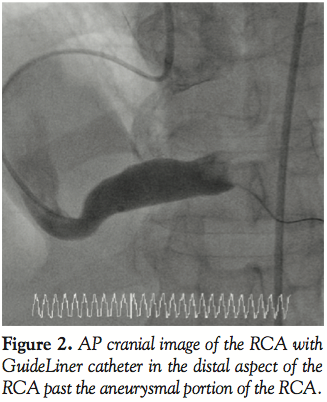

Case 3. A 65-year-old male presented with unstable angina. Diagnostic angiography demonstrated triple vessel coronary disease and normal ventricular function (Figure 7). After intervention on the RCA was performed, attention was turned to the circumflex artery (Figure 8). A 7 Fr EBU (Medtronic Vascular) guiding catheter was used for the intervention on the circumflex artery. A BMW (Abbott Vascular) guidewire was used to cross the lesion in the circumflex artery and angioplasty performed with a 3mm Voyager (Abbott Vascular) balloon. After

predilatation, there was difficulty advancing the stents through the calcified proximal vessel (Figure 8). A GuideLiner catheter was then advanced into the circumflex artery and this facilitated delivery of long drug-eluting stents to treat the stenosis successfully without need for a different wire or a different guiding catheter (Figure 9).

The GuideLiner catheter allowed a second vessel (circumflex) to be treated ad hoc by greatly simplifying a complex procedure and minimizing contrast load and radiation exposure to the patient. The patient was then brought back for treatment of the LAD chronic total occlusion. This enabled complete revascularization for this patient.

In the third, fourth, and fifth cases, the reason for the development of this device, facilitating distal stent delivery, is demonstrated. Commonly used methods to overcome difficulty with stent delivery include straightening of the vessel with a buddy wire, use of an anchor balloon, and using large diameter guiding catheters with more supportive curves. The GuideLiner facilitates delivery of stents to distal segments of the coronary vessel (Figures 4 and 5) by allowing safe deep vessel intubation. This provides the necessary extra back-up support needed for stent delivery. In an era when radial artery intervention is making a comeback into the mainstream, this may have added significance because the vast majority of cases via the radial artery are performed with 6 Fr guiding catheters. Also because of the angle of entry from the radial approach into the aortic sinus, coaxial guide placement is difficult. The GuideLiner catheter may allow for maintaining coaxial guide orientation. In case 3, a long circumflex artery stenosis was treated with deep engagement of the GuideLiner catheter to deliver 2 long DES as opposed to several shorter length drug-eluting stents. This may have incremental value in an era of cost containment by treating long lesions with fewer drug-eluting stents, thus lowering the cost per case.